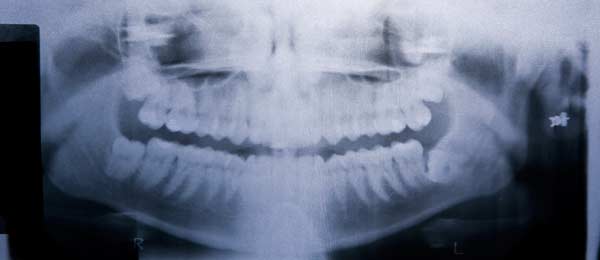

Impacted Tooth & Tooth Exposure

An impacted tooth is a tooth that fails to fully pass through the gums.

Impacted wisdom and cuspid (or canine) teeth are fairly common. To correct impacted teeth, there are a few treatment options. For impacted canine teeth, several treatment modalities are available. Orthodontics (braces) can be used to open space for proper eruption. Primary (baby) teeth can either be extracted or surgically exposed to allow for the placement of an orthodontic bracket to help align the teeth.

Wisdom Tooth Removal (3rd Molars)

A wisdom tooth that is deemed problematic is normally extracted to avoid any oral complications. To have a wisdom tooth removed, a small incision is made to open up the gum tissue over the tooth and remove any bone that is covering the tooth. Once the tooth is in view, it is grasped with a dental instrument, known as a forcep, and gently rocked back and forth to loosen it from the jaw bone and surrounding ligaments. Sometimes the tooth may need to be cut into smaller pieces to make it easier for removal. Stitches may be necessary after the removal of a wisdom tooth.

Partial Odontectomy

There are some cases in which an impacted wisdom tooth extraction brings the risk of nerve damage. In these cases, a partial odontectomy may be performed. This procedure involves removing the crown of the tooth but leaving the roots that are integrated with the bone and at risk of causing damage to the alveolar nerve. This intentional root detention reduces the risk of nerve damage.